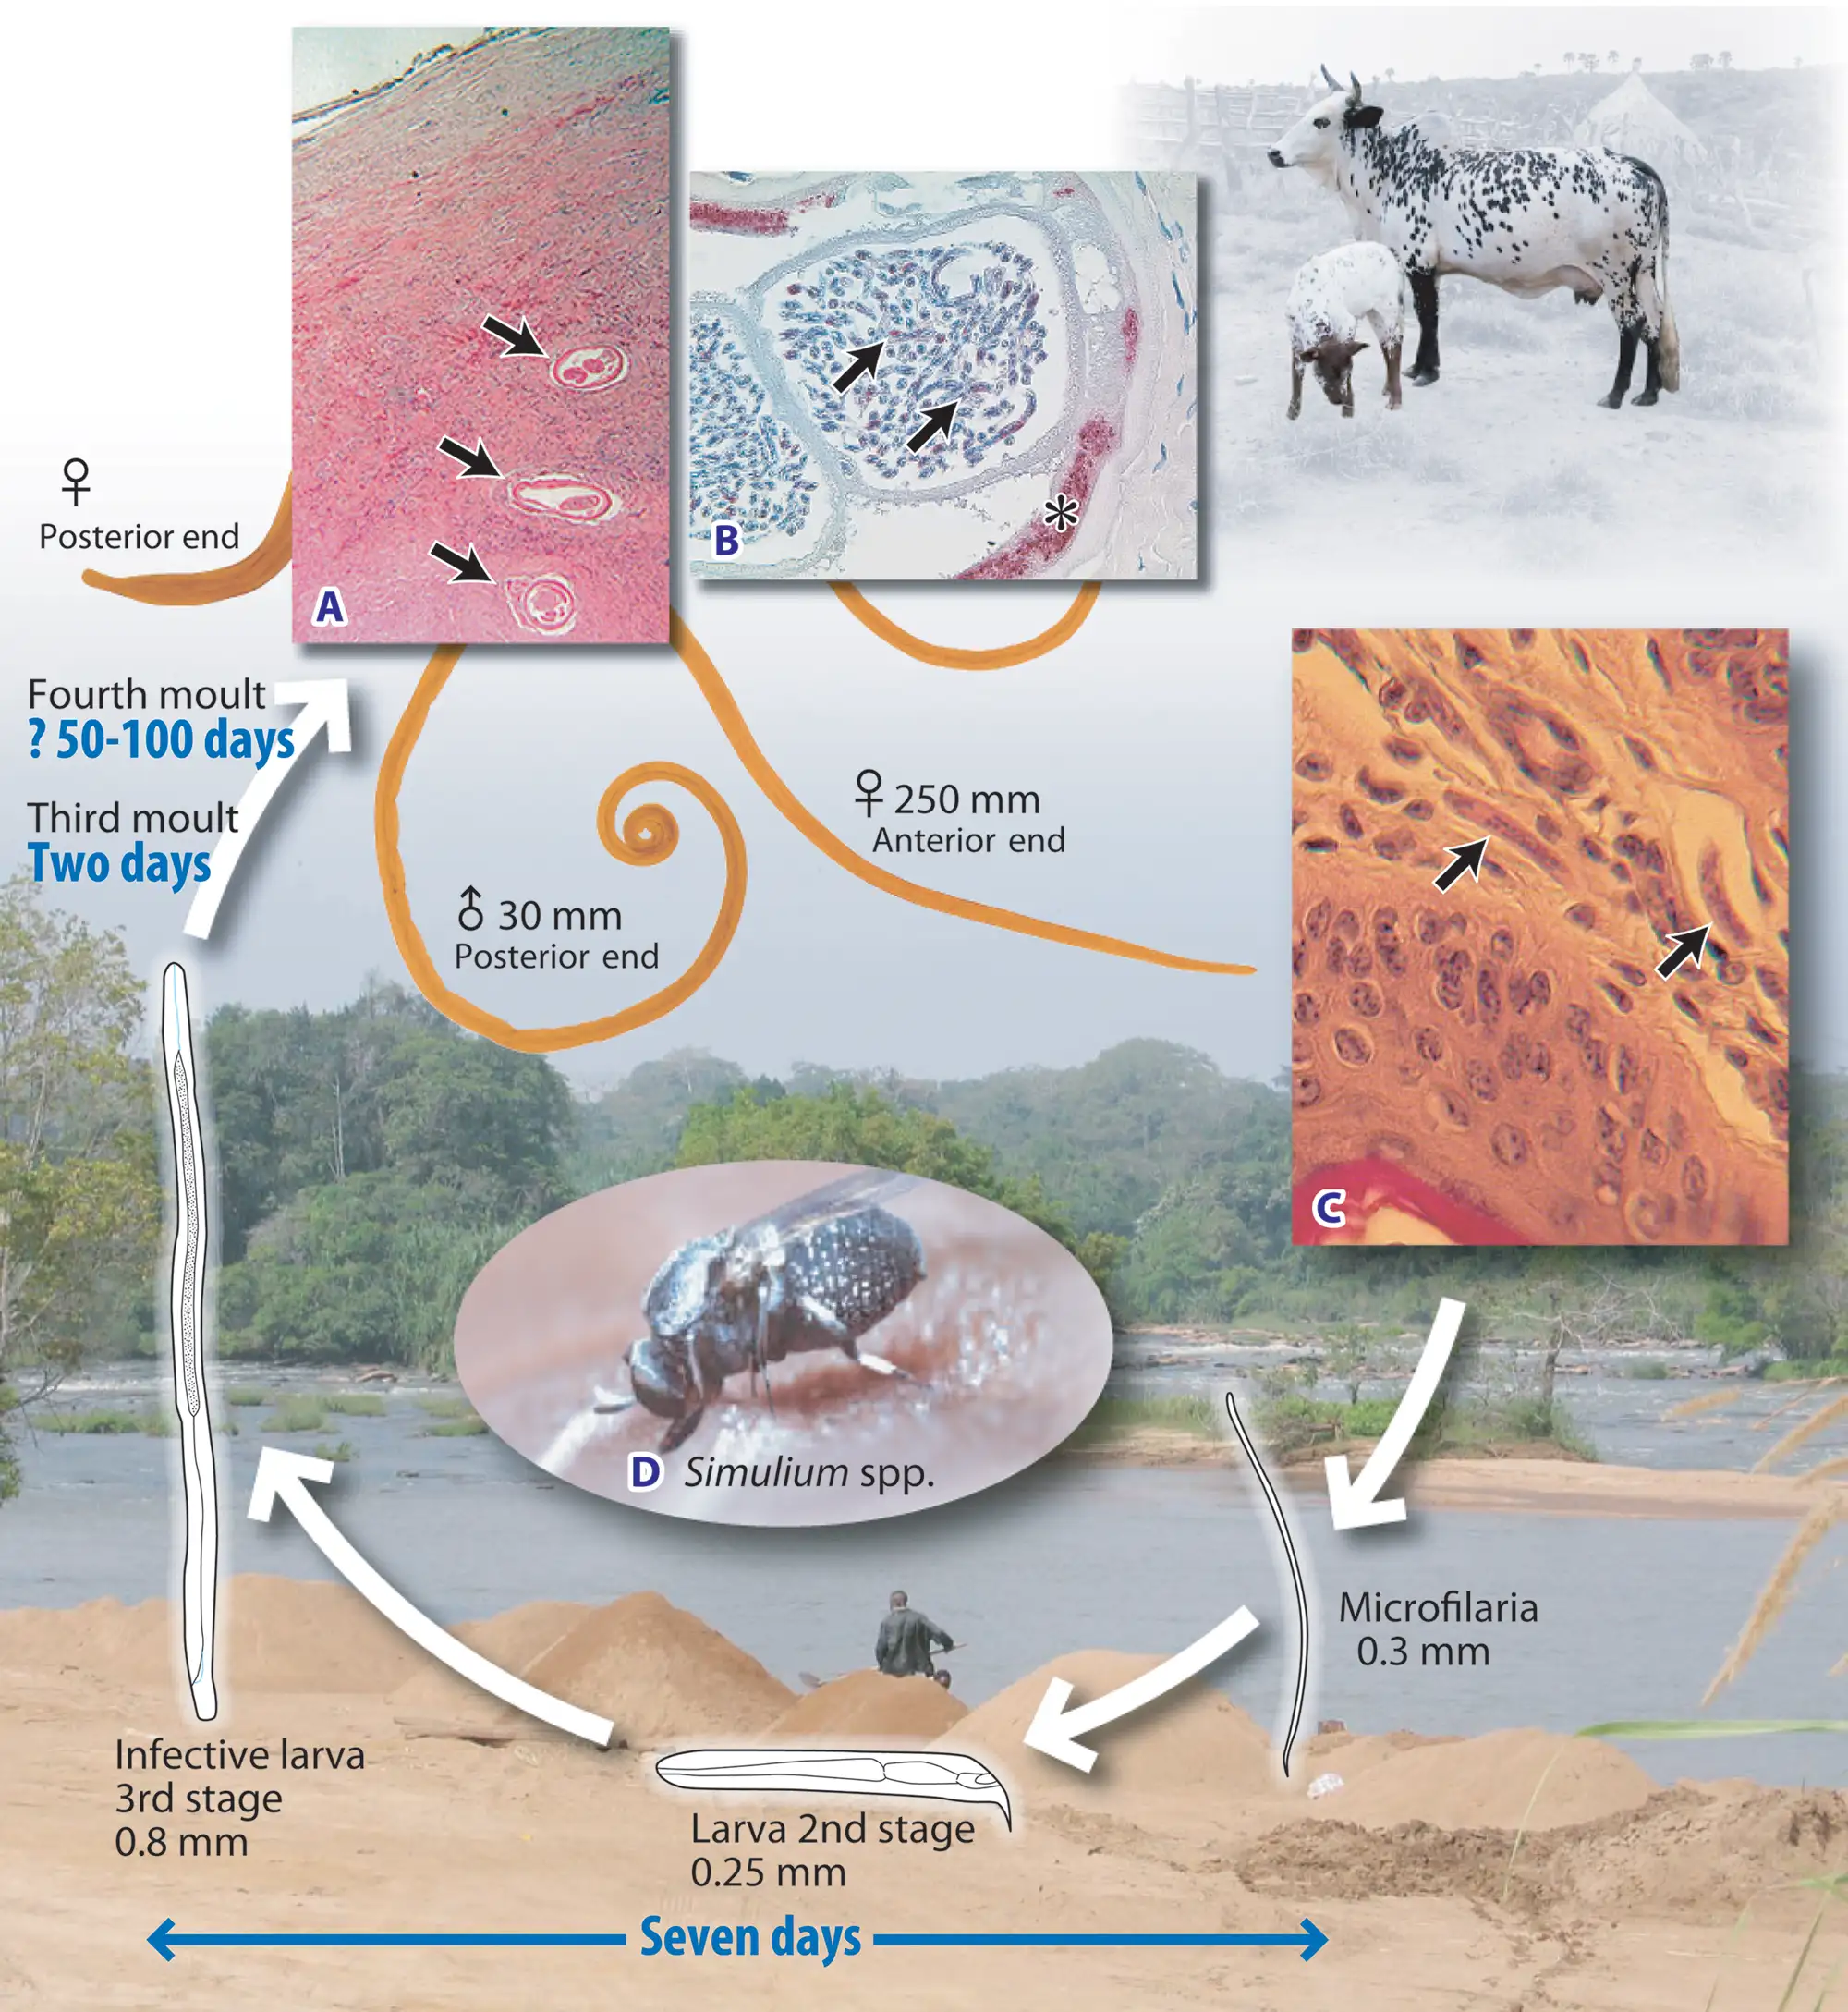

当雌性黑蝇叮咬已被感染的人类时,它会吸入含有微丝蚴的血液。这些微小的幼虫在黑蝇体内经历令人惊叹的蜕变。它们从蚊子的中肠穿越血腔,到达胸部肌肉,在那里经历两次蜕皮,最终发育成具有感染力的第三期幼虫。这个过程需要6至12天,期间黑蝇体内的温度和生化环境为幼虫提供着完美的培养皿。

成熟的感染性幼虫会向前迁移至黑蝇的头部和口器。当这只黑蝇再次叮咬人类时,幼虫便从口器中钻出,穿透人类的皮肤,开始它们在最终宿主体内长达十四年的寄生生涯。一只被感染的黑蝇可能携带数百条幼虫,而一次叮咬便足以完成传播。然而,黑蝇的传播效率其实相当低下——与传播疟疾的按蚊相比,需要数百次叮咬才能完成一次成功的传播。这解释了为什么河盲症主要影响长期生活在流行区的居民,而旅行者鲜少感染。

盘尾丝虫是地球上最成功的寄生虫之一。它的成虫形态可以在人体内存活长达14至15年,这是绝大多数寄生虫望尘莫及的寿命。更惊人的是,雌性成虫在其一生中可以产下数以百万计的微丝蚴,平均每天释放约1000至3000条幼虫。

当感染性幼虫进入人体皮肤后,它们会在数月内发育成熟。雄虫相对较小,体长约2至4厘米,细如发丝;而雌虫则可达30至50厘米长,直径约0.3至0.4毫米,是名副其实的"巨虫"。成虫并不四处游荡,它们将自己蜷曲成团,深埋在皮下结缔组织中,形成特征性的纤维结节——医学上称为"盘尾丝虫结节"或"蟠尾蚴瘤"。

然而,真正造成伤害的不是成虫,而是它们生产的微丝蚴。这些微小的幼虫体长仅约300微米,直径不到1微米,必须在显微镜下才能观察到。它们没有围鞘,身体纤细,尾部逐渐变尖。一旦离开母体,微丝蚴便开始在宿主的皮肤和皮下组织中四处迁移。